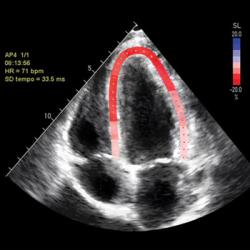

MECR imagine guideline

Download hier een samenvatting van de consensus van deskundigen met aanbevelingen voor multimodale beeldvorming bij cardiale amyloïdose.